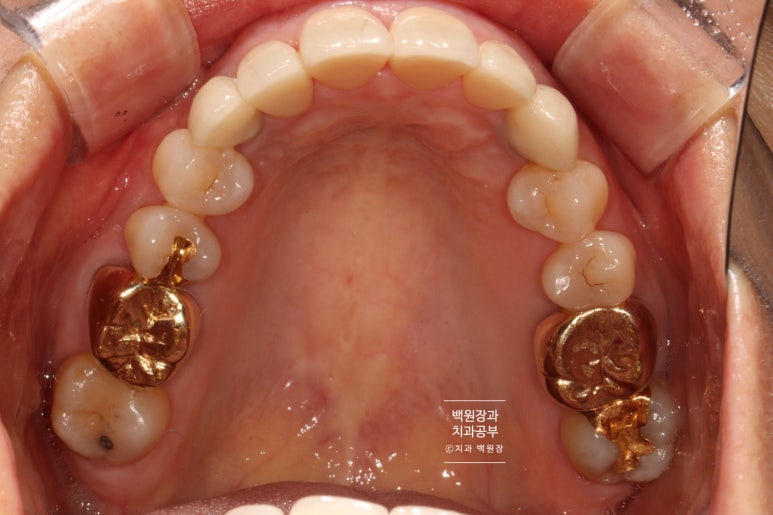

씹는면에서 바라보았을 때도 자연스러운 모양과 색상을 관찰할 수 있습니다.

오스템 임플란트의 네비게이션 임플란트 가이드 수술 시 이렇게 최종 보철물을 자연스럽게 만들 수 있답니다.